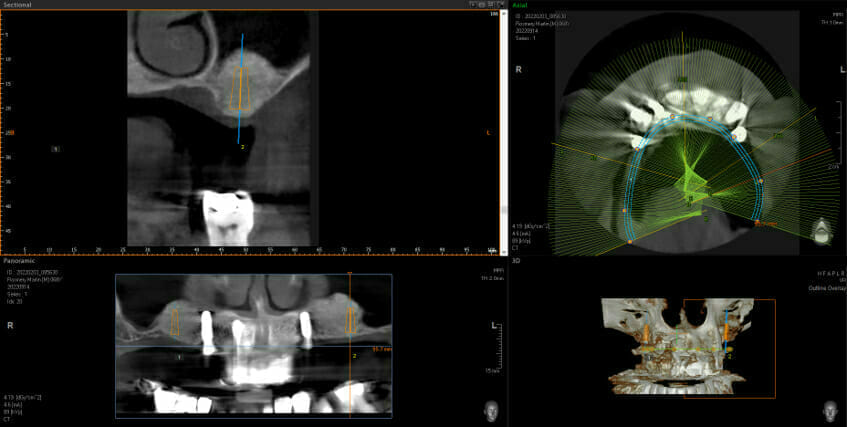

This shows big black areas where the sinuses are and shows that there is not enough bone to put the implants in (shown in orange). You don’t have to be an implantologist to see how much bone we have after the grafting. Now we can go ahead and place 2 implants each side at the back and this allows the addition of 3 new back teeth each side (using implant bridges means we still only need 4 implants, not 6, keeping surgical complication and costs down)

Before Sinus Bone Grafts